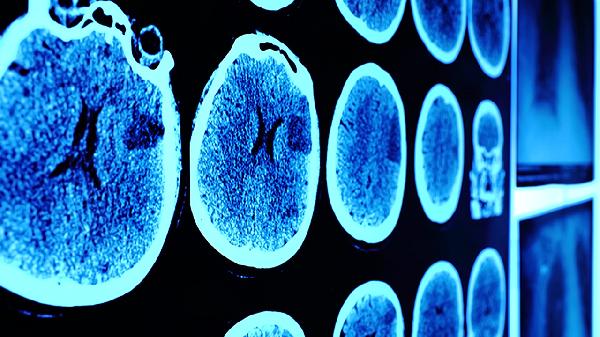

大脑中管记忆的区域主要有海马体、杏仁核、前额叶皮层、颞叶和顶叶。这些区域协同工作,负责记忆的形成、存储和提取。

海马体位于大脑内侧颞叶,是记忆形成的关键区域。它负责将短期记忆转化为长期记忆,尤其与情景记忆和空间记忆密切相关。海马体损伤可能导致顺行性遗忘,患者无法形成新的记忆。阿尔茨海默病早期常出现海马体萎缩,导致记忆力显著下降。海马体还参与记忆的整合过程,帮助将不同感官信息组合成完整记忆。

杏仁核位于颞叶前部,主要处理情绪记忆。它赋予记忆情感色彩,增强重要事件的记忆强度。恐惧记忆的形成特别依赖杏仁核的激活。创伤后应激障碍患者的杏仁核往往过度活跃,导致创伤记忆反复闪回。杏仁核还通过调节应激激素分泌影响记忆巩固过程。

前额叶皮层位于额叶前部,负责工作记忆和执行功能。它像临时存储空间,暂时保存正在处理的信息。前额叶损伤会导致计划能力和注意力下降。该区域还参与记忆的提取和回忆策略选择,帮助有意识地检索记忆。随着年龄增长,前额叶功能衰退会影响记忆检索效率。

颞叶特别是外侧颞叶皮层,是长期记忆存储的重要部位。语义记忆和程序性记忆主要分布在此区域。颞叶癫痫发作可能引发似曾相识感或记忆闪回。该区域还包含听觉联合皮层,负责与声音相关的记忆处理。颞叶与海马体有密集神经连接,共同完成记忆编码和巩固。

顶叶特别是后顶叶皮层,参与空间记忆和身体感知记忆。它帮助构建心理地图和空间关系记忆。顶叶损伤可能导致空间定向障碍和记忆提取困难。该区域还整合视觉和体感信息,形成多感官记忆表征。顶叶与工作记忆的视觉空间组件密切相关。